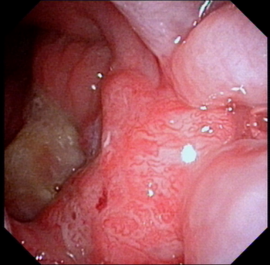

下咽癌颈淋巴结转移

下咽部淋巴组织丰富,较易发生淋巴结转移,早期常转移至同侧颈动脉三角区颈深部淋巴结,多为分化程度较差的癌。而且由于下咽部位置隐蔽,常常原发灶不易发现,还有转移灶很大,原发灶很小的情况。